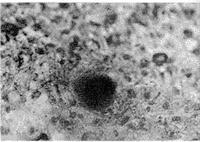

3、電鏡檢查:腎小球基底膜內稀疏層和系膜區有顆粒狀物質沉積系膜基質增寬和腎小球基底膜增厚;腎小管基底膜和腎間質血管基底膜可見密集顆粒電子緻密物。